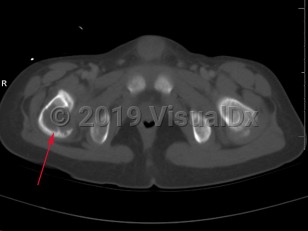

The clinical presentation of EG depends largely on the location affected. EG is most often confined to the axial skeleton. EGs are often asymptomatic and found incidentally, or may initially present with pain and swelling of the affected area, with or without decreased range of motion. Commonly affected areas of the skeleton include (in order of frequency): skull, femur, pelvis, mandible, clavicle, ribs, and long bones (of the diaphysis and metaphysis).